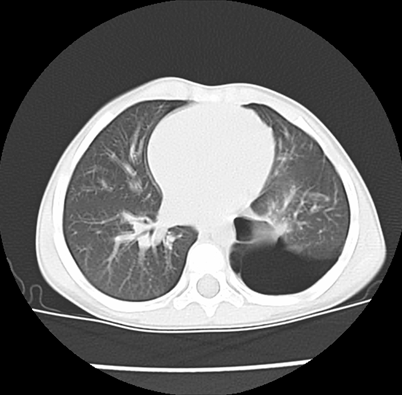

We asked for a Chest CT scan